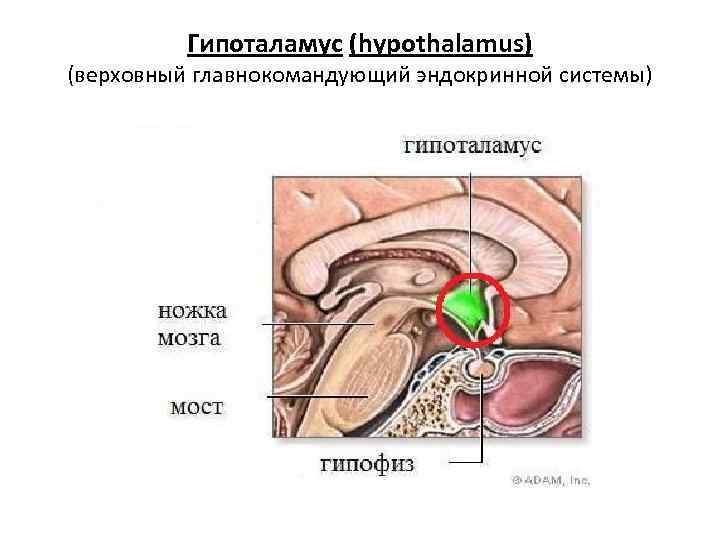

Как работает центр насыщения в гипоталамусе: визуальные иллюстрации